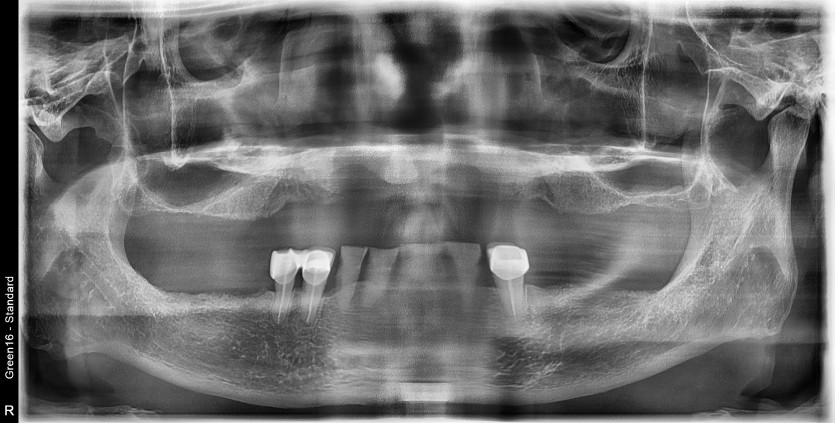

만 68세 상악 전체 임플란트 증례(하악 일부)

상악 전체 임플란트 증례입니다.(하악 일부)

15개의 임플란트로 완성하였습니다.